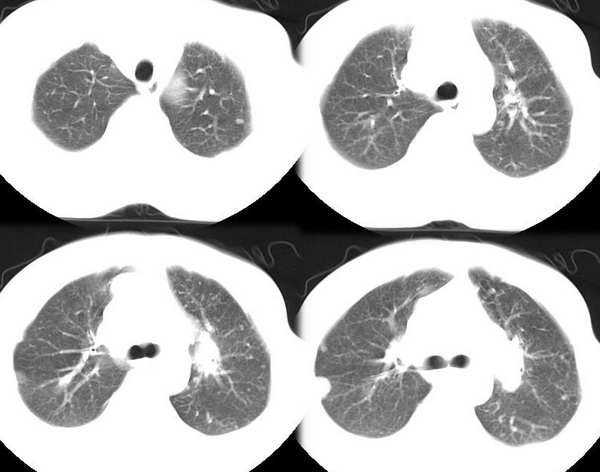

男35y,皮鞋工10余年,近月来发烧,咳血,胸痛,半年前胸片正常,左锁骨上淋巴结肿大,按炎性治疗无效。行ct检查。发平扫片暂无增强片

双肺散在分布多发大小不等圆形、类圆形结节影,多数边界清晰,部分有融合,以肺周边部(胸膜下、隔上及纵隔旁)为著;纵隔肺门淋巴结增大;双侧少量胸水。

影像:两肺散在分布多发大小不等圆形、类圆形结节影,多数边界清晰,部分有融合,纵隔肺门淋巴结增大;双侧少量胸水。

影像:两肺散在分布多发大小不等圆形、类圆形结节影,以近胸膜面为明显,多数边界清晰,部分有融合,纵隔肺门淋巴结增大;双侧少量胸水。